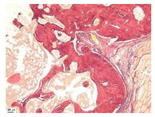

| Point | Type of Microscopy | ||||

|---|---|---|---|---|---|

| Standard Light | Standard Light | Polarization | Standard Light | Phase Contrast | |

| Staining with Hematoxylin–Eosin | Staining with Picrosirius Red | Staining with Picrosirius Red | Staining with Hematoxylin–Eosin | Staining with Hematoxylin–Eosin | |

| 3 | ![]() | ![]() | ![]() | ![]() | ![]() |

| 5 | ![]() | ![]() | ![]() | ![]() | ![]() |

| 8 | ![]() | ![]() | ![]() | ![]() | ![]() |